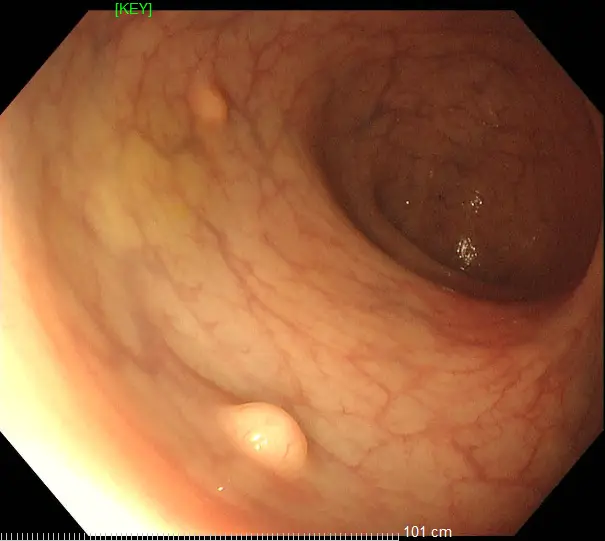

36歲的王先生在蘇州高新區人民醫院行胃腸鏡檢查時,發現直腸裡有1個息肉和2個黏膜下半球型隆起,表面光滑、顏色發黃,大小直徑約1.0cm,當時便做了超聲內鏡檢查,顯示2個隆起的腫物位於直腸黏膜下層,可能是神經內分泌腫瘤,1個粘膜層隆起的息肉可能是腺瘤腫瘤。消化科團隊立即為王先生進行了腸鏡下黏膜剝離術切除了2個粘膜下腫物,同時進行了腸鏡下粘膜切除術解決了1個腺瘤樣息肉,術後病理顯示:2個是神經內分泌瘤NET G1,切緣乾淨。1個管狀腺瘤伴低階別上皮內瘤變(屬於癌前病變),目前王先生恢復良好,已順利出院。

直腸神經內分泌瘤內鏡下治療的適應證包括腫瘤直徑<1 cm,侷限於黏膜或黏膜下層(T1期)的G1/G2級病變腫瘤。對直徑1-2cm的腫瘤,兼顧根治及功能保全,透過內鏡及影像學充分評估後選擇治療方式。內鏡下黏膜剝離術(ESD)是一項先進的內鏡下四級微創技術,醫生透過電刀,在內鏡下實現對胃腸道表淺病變的治癒性切除。